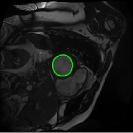

4.4 Comparison with cardic MR images for left ventricle segmentation

In this section, we continue to conduct experiments on cardiac MR images. However, we focus on the right ventricle, which is equally important as the left ventricle in cardiac MR diagnoses. In the near short-axis view, the left ventricle has a crescent shape, while the right ventricle is closer to circular. This does not imply that the right ventricle is easier to segment; in the MR images we use, the right ventricle often shows low-signal-intensity shadows, which may be caused by the imaging characteristics of certain tissues or fluids, leading to interference in segmentation. Moreover, there is a layer of myocardial tissue surrounding the right ventricle that overlaps with the boundary of the right ventricle, posing challenges for accurate identification.

Fig. 8 presents the segmentation results of the right ventricle from the DRLSE-ADMM [WALI2023109105], ABC model [WENG2021115633], RESLS [8765635], the RefLSM, and the ground truth. The results from the DRLSE-ADMM model in the 1st row reveal severe local minima due to low-signal-intensity shadows in the right ventricle. Additionally, both the ABC and RESLS models fail to correctly identify the right ventricle boundary because of the interference from surrounding myocardial tissue, as seen in the 1st and 3rd columns of Fig.8. In comparison, the proposed model gets more satisfactory segmentation results that are closer to the ground truth. Similarly, we evaluate the segmentation performance of all models by calculating the Dice and Precision values and drawing Fig. 9. This overlay plot presents the best, median and worst segmentation results, along with the overall range of outcomes that it is clear that the proposed model segments the right ventricle with greater accuracy than the other models and performs well in different images.